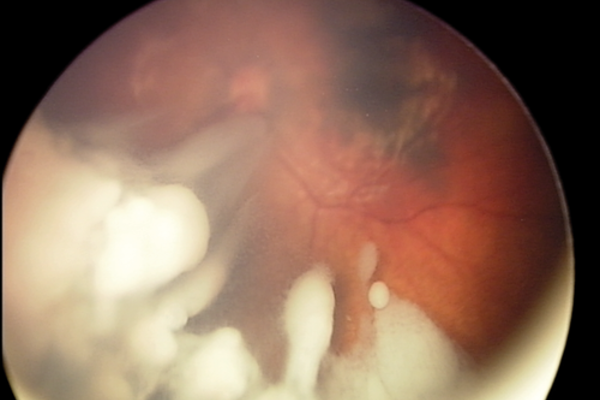

Sickle cell eye disease: an overview of vitreoretinal complications and their surgical management